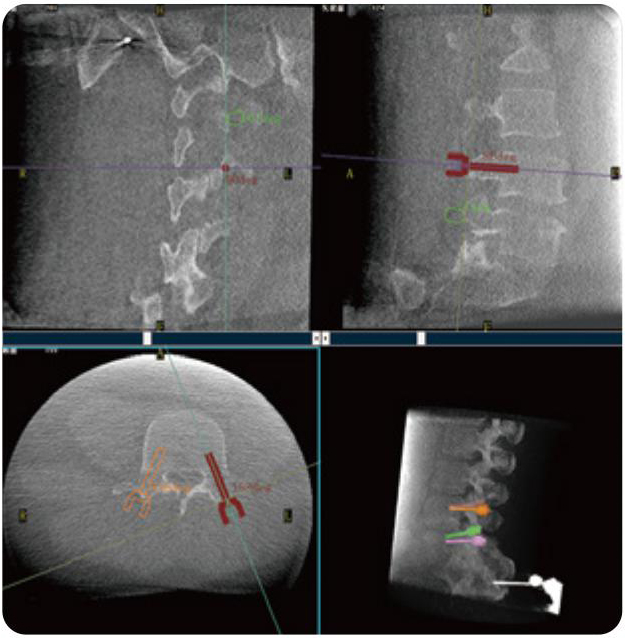

PL300B可應(yīng)用于多節(jié)段脊柱外科手術(shù),輔助醫(yī)生定位病灶部位,為脊柱外科手術(shù)(經(jīng)皮椎體成形術(shù)、椎弓根螺釘內(nèi)固定術(shù)等術(shù)式)提供術(shù)前手術(shù)流程規(guī)劃、入釘位置、角度可視化引導(dǎo),模擬仿真入釘輔助。

PL300B搭配普愛(ài)醫(yī)療自主研發(fā)生產(chǎn)的平板3D C形臂,借助一體化自適應(yīng)配準(zhǔn)( 軌跡配準(zhǔn))技術(shù),通過(guò)追蹤C(jī)形臂三維采集軌跡,自動(dòng)完成圖像坐標(biāo)建立和系統(tǒng)坐標(biāo)配準(zhǔn)。配準(zhǔn)精度更高,操作步驟少,系統(tǒng)運(yùn)作效率高。